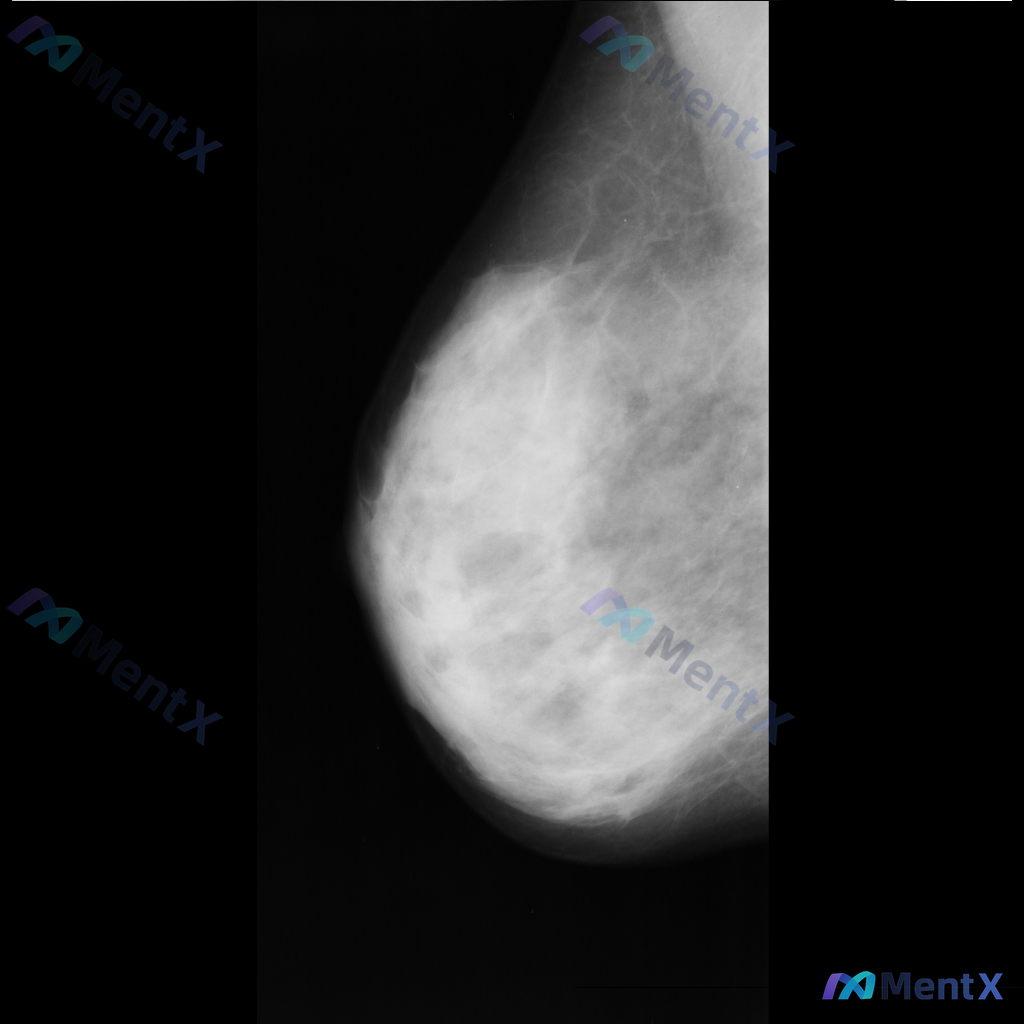

各位老师好,这里有一张乳腺钼靶影像(image: mdb281.png),影像中可见一些异常表现,想请大家一起讨论一下。

整理到一份单侧乳腺钼靶MLO位的影像资料,想和大家讨论一下初步判断思路。 影像基本情况 - 投照位置:单侧乳腺MLO位 - 主要表现:乳腺组织不均匀致密,ACR BI-RADS c类;在致密的腺体背景下,可见部分区域的致密影,但边界比较模糊,暂不能明确界定为独立肿块。 目前只有这一个位置的影像资料,...